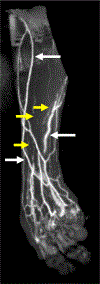

Lymphedema is a devastating disease that has no cure. Management of lymphedema has evolved rapidly over the past two decades with the advent of surgeries that can ameliorate symptoms. MRI has played an increasingly important role in the diagnosis and evaluation of lymphedema, as it provides high spatial resolution of the distribution and severity of soft tissue edema, characterizes diseased lymphatic channels, and assesses secondary effects such as fat hypertrophy. Many different MR techniques have been developed for the evaluation of lymphedema, and the modality can be tailored to suit the needs of a lymphatic clinic. In this review article we provide an overview of lymphedema, current management options, and the current role of MRI in lymphedema diagnosis and management. EVIDENCE LEVEL: 5 TECHNICAL EFFICACY: Stage 5.